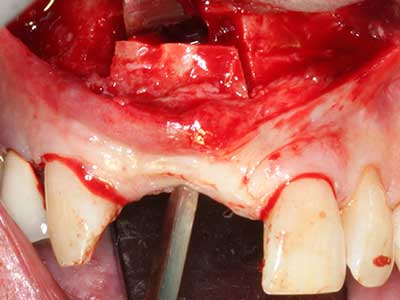

En la extracción de bloques óseos la piezocirugía también presenta ventajas adicionales: Además de la alta precisión en la osteotomía que ya se ha descrito antes, se ha comprobado que el uso de los delgados insertos de sierra resulta especialmente cuidadosas con el hueso. Frente a esto, sobre todo cuando se usan las fresas de Lindemann, cabe esperar pérdidas en la extracción significativamente más altas debido al mayor grosor de la parte frontal del cabezal (Lakshmiganthan, Gokulanathan et al. 2012). La separación basal que se necesita en particular en los injertos de bloque extraídos de forma retromolar se ve facilitada mediante sierras perpendiculares especialmente previstas a tal fin, lo que permite considerar que la cirugía piezoeléctrica es un procedimiento preciso y seguro para la obtención de bloques de hueso en el área retromolar (Happe 2007) (fig. 1-12).

El tejido óseo no solo tiene un contenido puramente mineral, sino que también presenta una importante proporción de fibras de colágeno. Esto no solo garantiza una buena resistencia a la presión, sino también una cierta flexibilidad, que puede aprovecharse para la realización de aumentos. En la plastia de expansión clásica a efectos de una partición ósea, la cresta maxilar atrofiada se divide en su eje longitudinal y, tras alcanzar una profundidad de osteotomía suficiente, se extiende con cuidado (fig. 13-16), en un caso ideal sin desperiostizar de forma visible el maxilar (Brugnami, Caiazzo et al. 2014, Stricker, Fleiner et al. 2014). Los sistemas de tornillos y placas con distancia de expansión creciente han demostrado su eficacia para distanciar entre sí las dos tablas óseas por debajo del umbral de rotura. Por regla general, se requieren anchuras de hueso residual de al menos 3 a 4 mm (Chiapasco, Zaniboni et al. 2006) para garantizar una flexibilidad y una cobertura ósea suficientes de los implantes que van a incorporarse. En caso necesario, una osteotomía de descarga vertical unilateral o bilateral puede mejorar la flexibilidad. Como alternativa a la técnica clásica se ha descrito una combinación con otras técnicas de aumento, sobre todo en la parte bucal.

Con el uso de sierras piezoeléctricas la división se efectúa de forma especialmente cuidadosa y sin pérdidas importantes de las dimensiones, por lo que no se han encontrado diferencias significativas entre los implantes realizados en el maxilar dividido y en la cresta alveolar no deficitaria (Chiapasco, Zaniboni et al. 2006, Danza, Guidi et al. 2009). No obstante, precisamente en la partición profunda y limitada de forma local, es preciso asegurarse de que exista una adecuada irrigación por agua para evitar que se produzcan sobrecargas térmicas en las áreas de osteotomía apical.